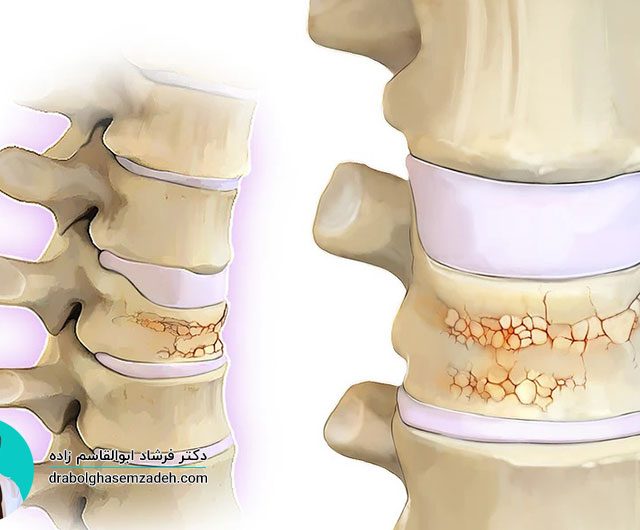

روماتیسم مفصلی نوعی بیماری است که موجب درد، التهاب و تورم مفصل های بدن می شود و مفصل لگن نیز از این قاعده مستثنی نیست. درمان روماتیسم لگن می تواند از مشکلات بسیاری از جمله تخریب مفصل لگن پیشگیری کند. این بیماری در زنان شایع تر از مردان است و علائم بیشتری از خود نشان […]...